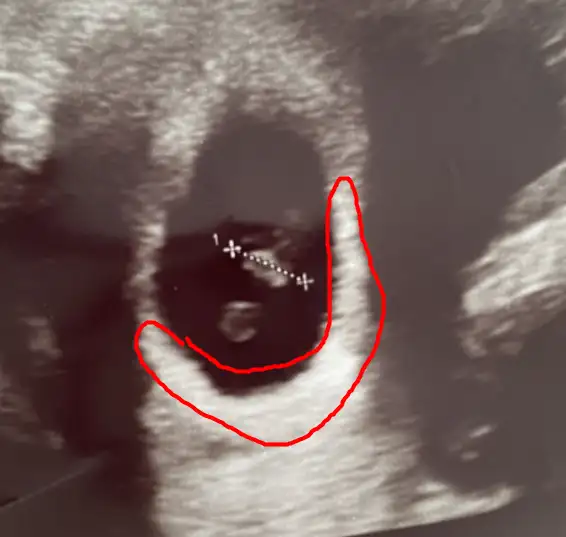

plesantası sağda bu yüzden kız aşkım :D

melegim can melegim can kız dedı :D bende ramzı teorısıne gore plesanta sağda ıdı oyuzden kız dedım D: bakalım tutacakmı melegım pozıtıfbırınde de tutturmustu :D